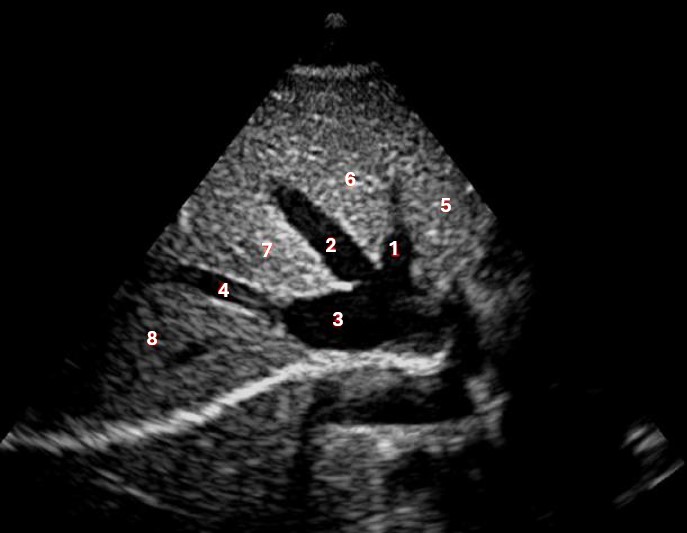

Left hepatic vein

What lobe of the liver is indicated by #1?

Posterior right lobe

Which of the following structures is labeled #2?

Middle hepatic vein

What structure/vessel is indicated by #6?

Superior mesenteric artery

What structure/vessel is indicated by #2?

Left portal vein

Which of the following structures is labeled #3?

IVC

Which of the following structures is labeled #6?

Medial left lobe

What structures last vessel is indicated by #4?

Which of the following structures is labeled #4?

Right hepatic vein

Which structure/vessel is indicated by #5?

Lateral left lobe

Which of the following structures is labeled #8?